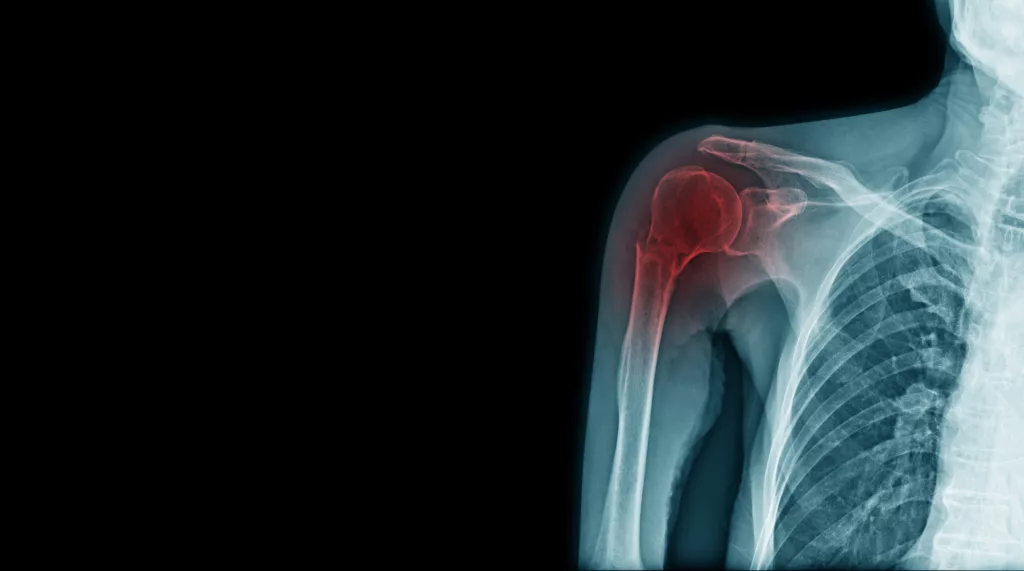

Fracture de l’extrémité proximale de l’humérus

L’extrémité proximale de l’humérus correspond à la partie haute de l’os du bras, au voisinage immédiat de l’épaule. Une fracture à ce niveau est fréquente, notamment après une chute, et peut concerner le col chirurgical, les tubérosités ou la tête humérale.